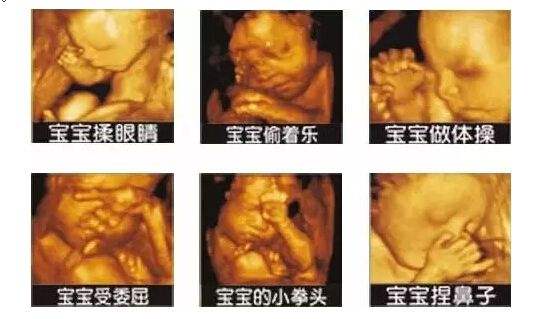

而彩超四维则是在三维的基础上,加上了时间矢量,让我们能在屏幕上清楚地看到,您未出生的宝宝实时动态活动图像。我们可以看到宝宝的表情,再对宝宝进行拍照,他们打哈欠、吃手指的照片就这样保存下来了!